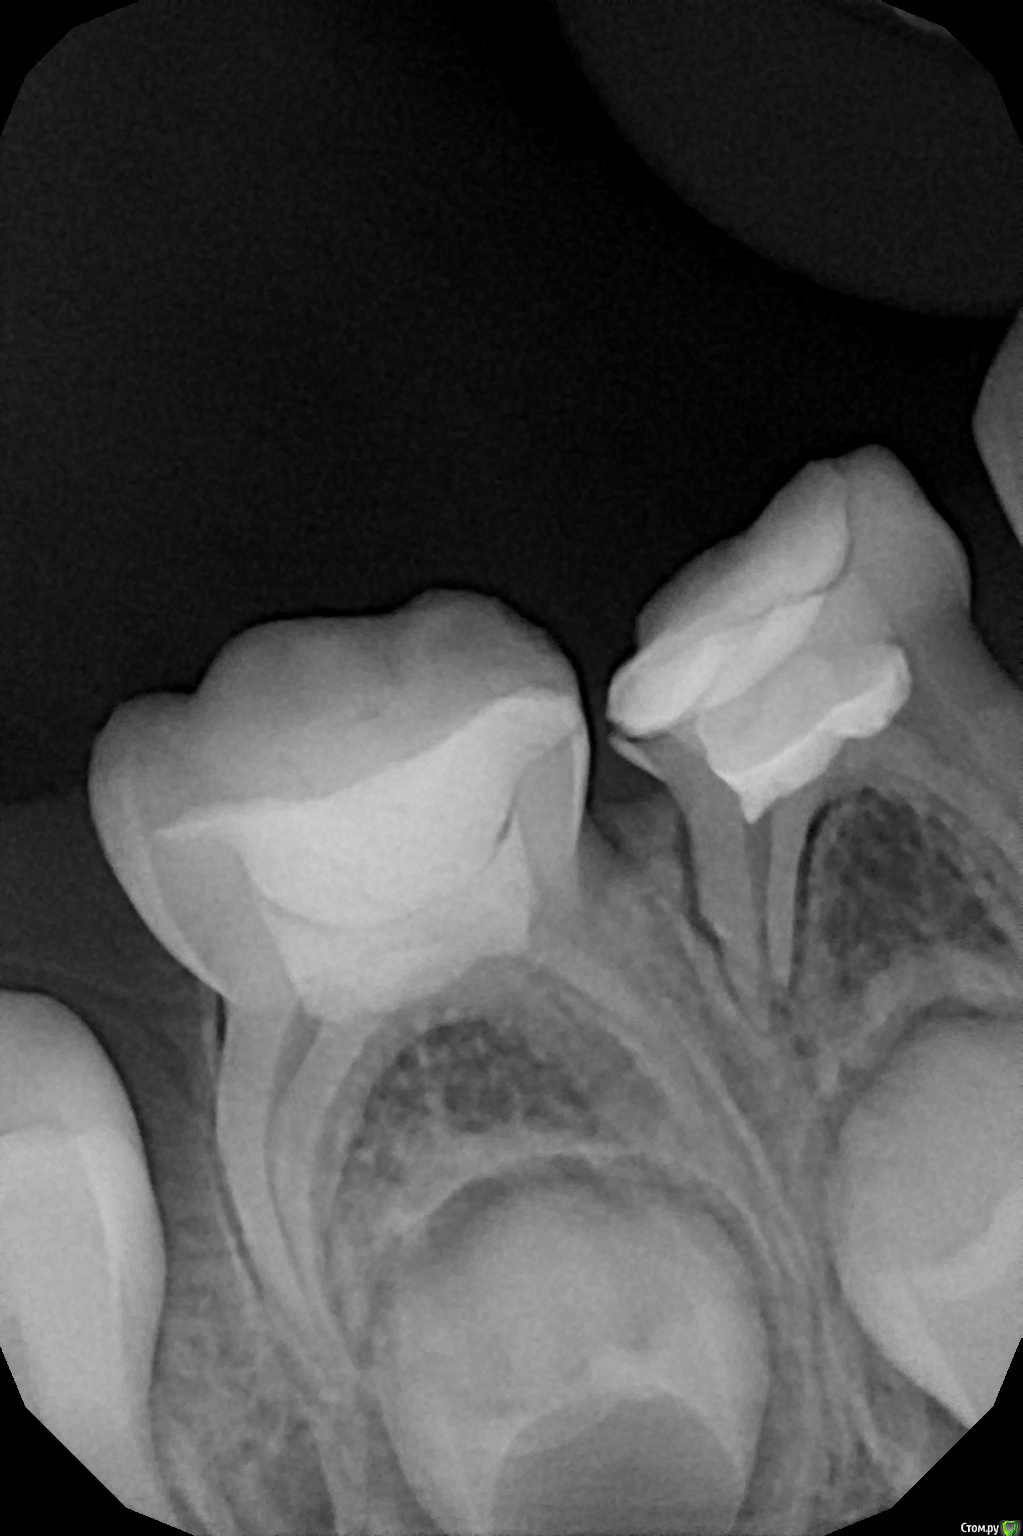

Этери Сафинос Опубликовано 18 октября, 2020 Поделиться Опубликовано 18 октября, 2020 Здравствуйте. Обратился ребенок 5 лет. 7.4 и 7.5 резорциненные. Отек в области этих зубов. Перкуссия на 7.4 и 7.5 безболезненная, подвижность 1 степени на обоих. На переходной отек больше в области 7.4, при пальпации безболезненный (так ребенок говорит). Открыли пока только 7.4, был гной, кровь сгустками, промыли через дистальный канал, много вышло каки, после промывания отек сдулся. Закрыли пока с кальсептом с йодоформом. На оптг огромная киста в области обоих зубов, стоит ли продолжать лечение зубов, открывать 7.5, что целесообразнее удалить или пытаться сохранить? Зачатки постоянных зубов в опасности, как бы вы поступили? Ссылка на комментарий